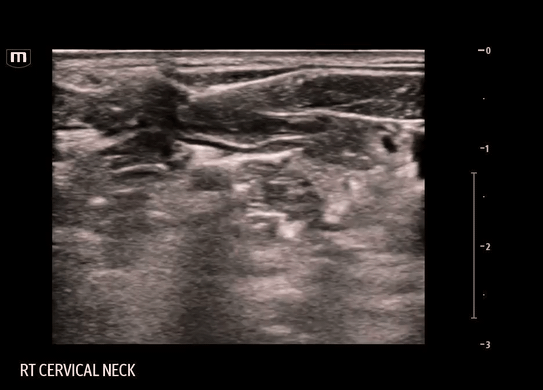

• Using a linear probe, start scanning over the SCM at the level of the thyroid cartilage and slide laterally until visualization of the edge of the sternocleidomastoid muscle (SCM), underlying levator scapulae (LS) muscle, internal jugular vein (IJV) and carotid artery (CA)

• SCP nerve bundle may or may not be present below the SCM

• This procedure is done with in-line technique and the target is the fascial plane just deep to the SCM and superficial to the prevertebral fascia containing the LSM and scalene muscles.

Clips from our block:

FYI: During this particular block, the needle entered from the same side as the SCM, contrary to the usual technique. This was done to avoid a vessel on the other side. The block should routinely be done as described above.